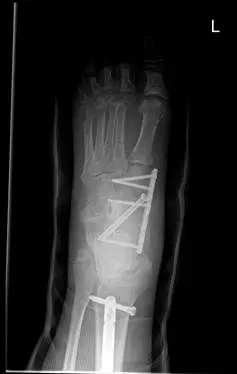

These are pics of an open midfoot fracture and dislocation after a motor vehicle accident.

These are pics of the external fixator on to hold temporary reduction prior to internal fixation

These are pics of the plate and screws stabilizing the fractures after ex fix was removed. An IM rod was also placed for a tibia fracture.